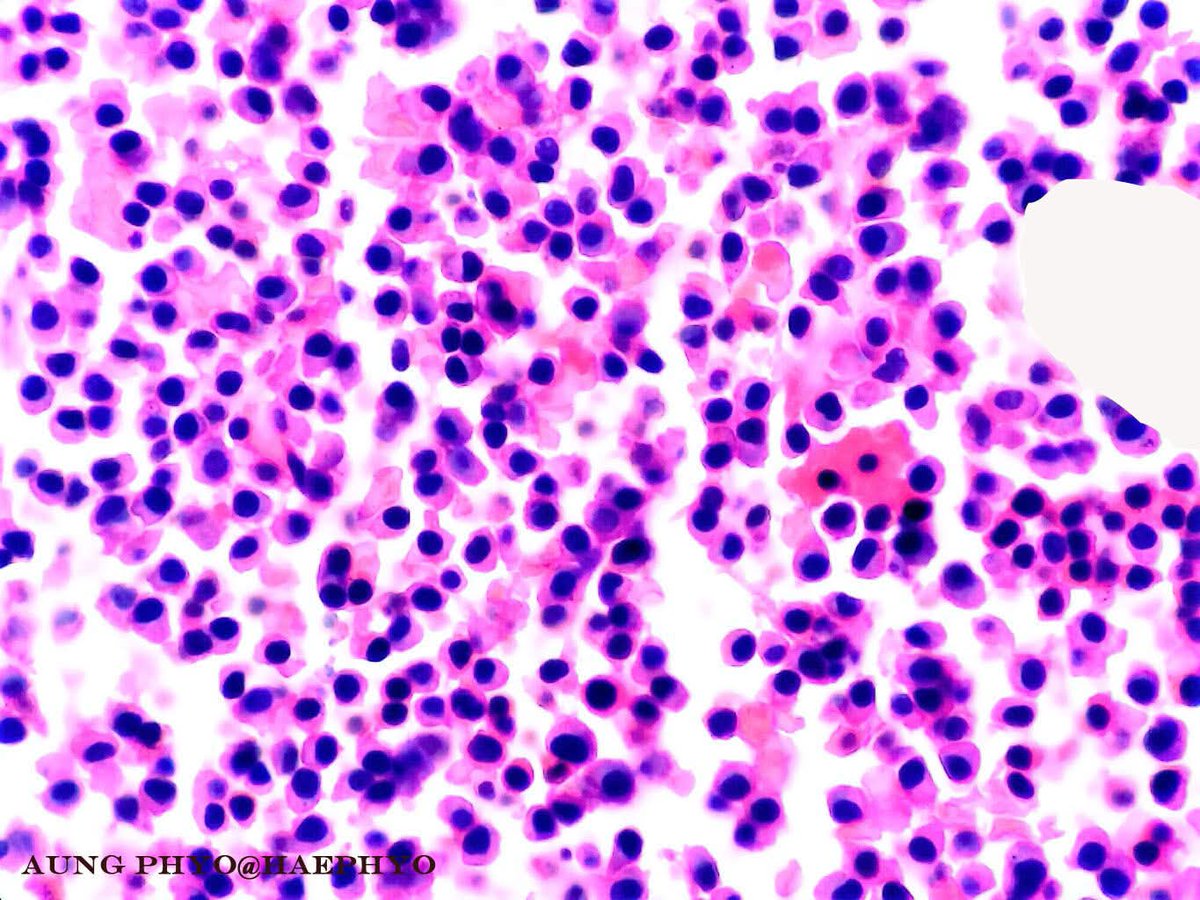

Multiple myeloma. The blue smear and RBC rouleaux created by paraproteins and clonal and neoplastic plasma cells featuring varying morphologies. Patient presents with pancytopenia which is a poor prognostic factor. #pathology #hemepath #myeloma